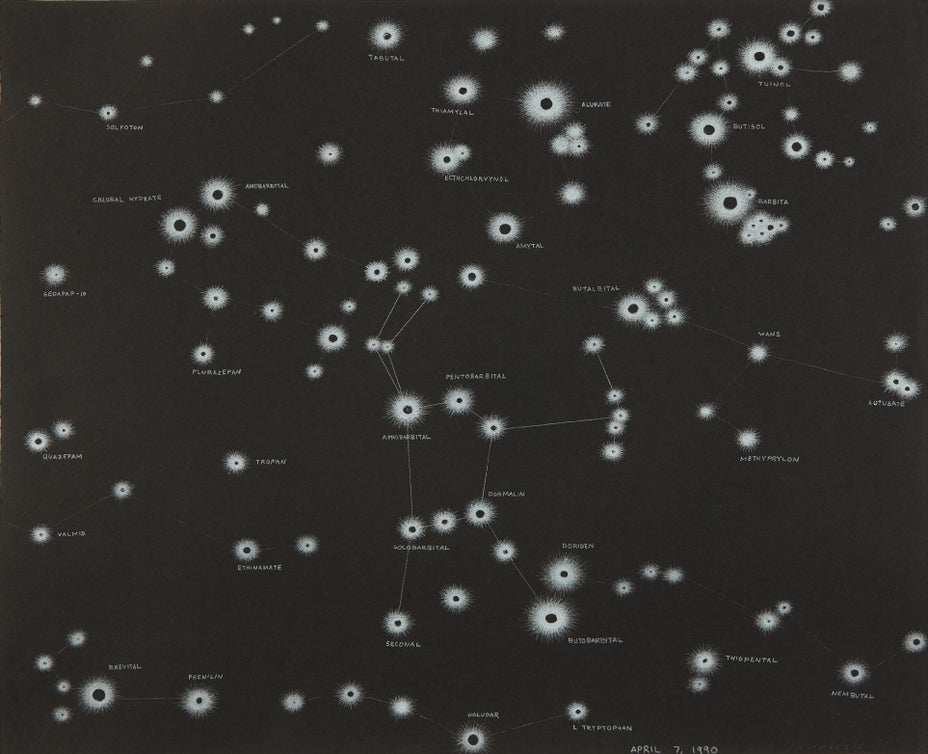

費雷德.托馬塞利

Sleeping pills - constellations of Orion, Perseus, Gemini, Taurus, Pliedies, the kid

prismacolor on paper

14 1/4 x 17 1/2 in. (36.2 x 44.5 cm)

Signed and dated "April 7, 1990 Tomaselli" lower right.